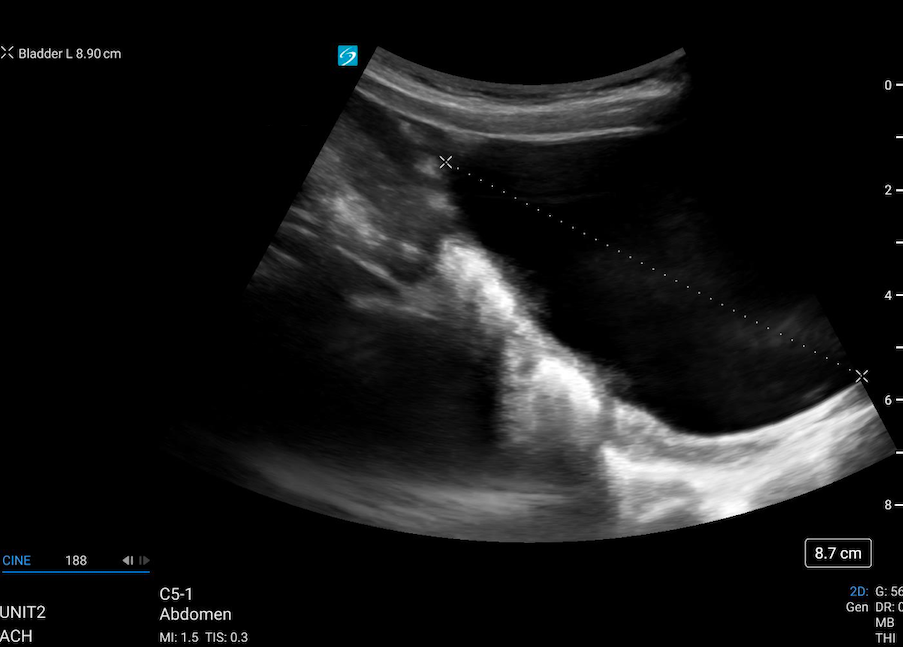

Bladder Volume Technique:

Bladder volume can be determined non-invasively by measuring the bladder in its maximal width, depth, and length. Bladder volume can be calculated both pre- and post-void.

1. Scan the bladder in two planes to obtain three unique measurements (Figure 2)

> Width: In the transverse plane, measure the diameter between the lateral walls to obtain the width.

> Depth (height): is the anteroposterior diameter, which can be obtained in the transverse or sagittal plane. Choose just one plane for this measurement.

Length: is the craniocaudal diameter, which is obtained by measuring from the superior to inferior wall of the bladder in the sagittal plane.

2. Calculate Volume

> Most current machines contain automated calculators for volume measurement.

> As an alternative, the simple formula (LX W X D X 0.7) can be used to estimate bladder volume.

– However, because of the inherent variability of bladder shape and the variation in this shape with differing degrees of filling, bladder volume measurements obtained in this fashion may have an error rate between 15% and 35% [10].

Figure 2: Measurements for bladder volume in transverse and sagittal planes [11]

Figure 3 & 4: Caliper placement for bladder volume in the transverse and sagittal planes.